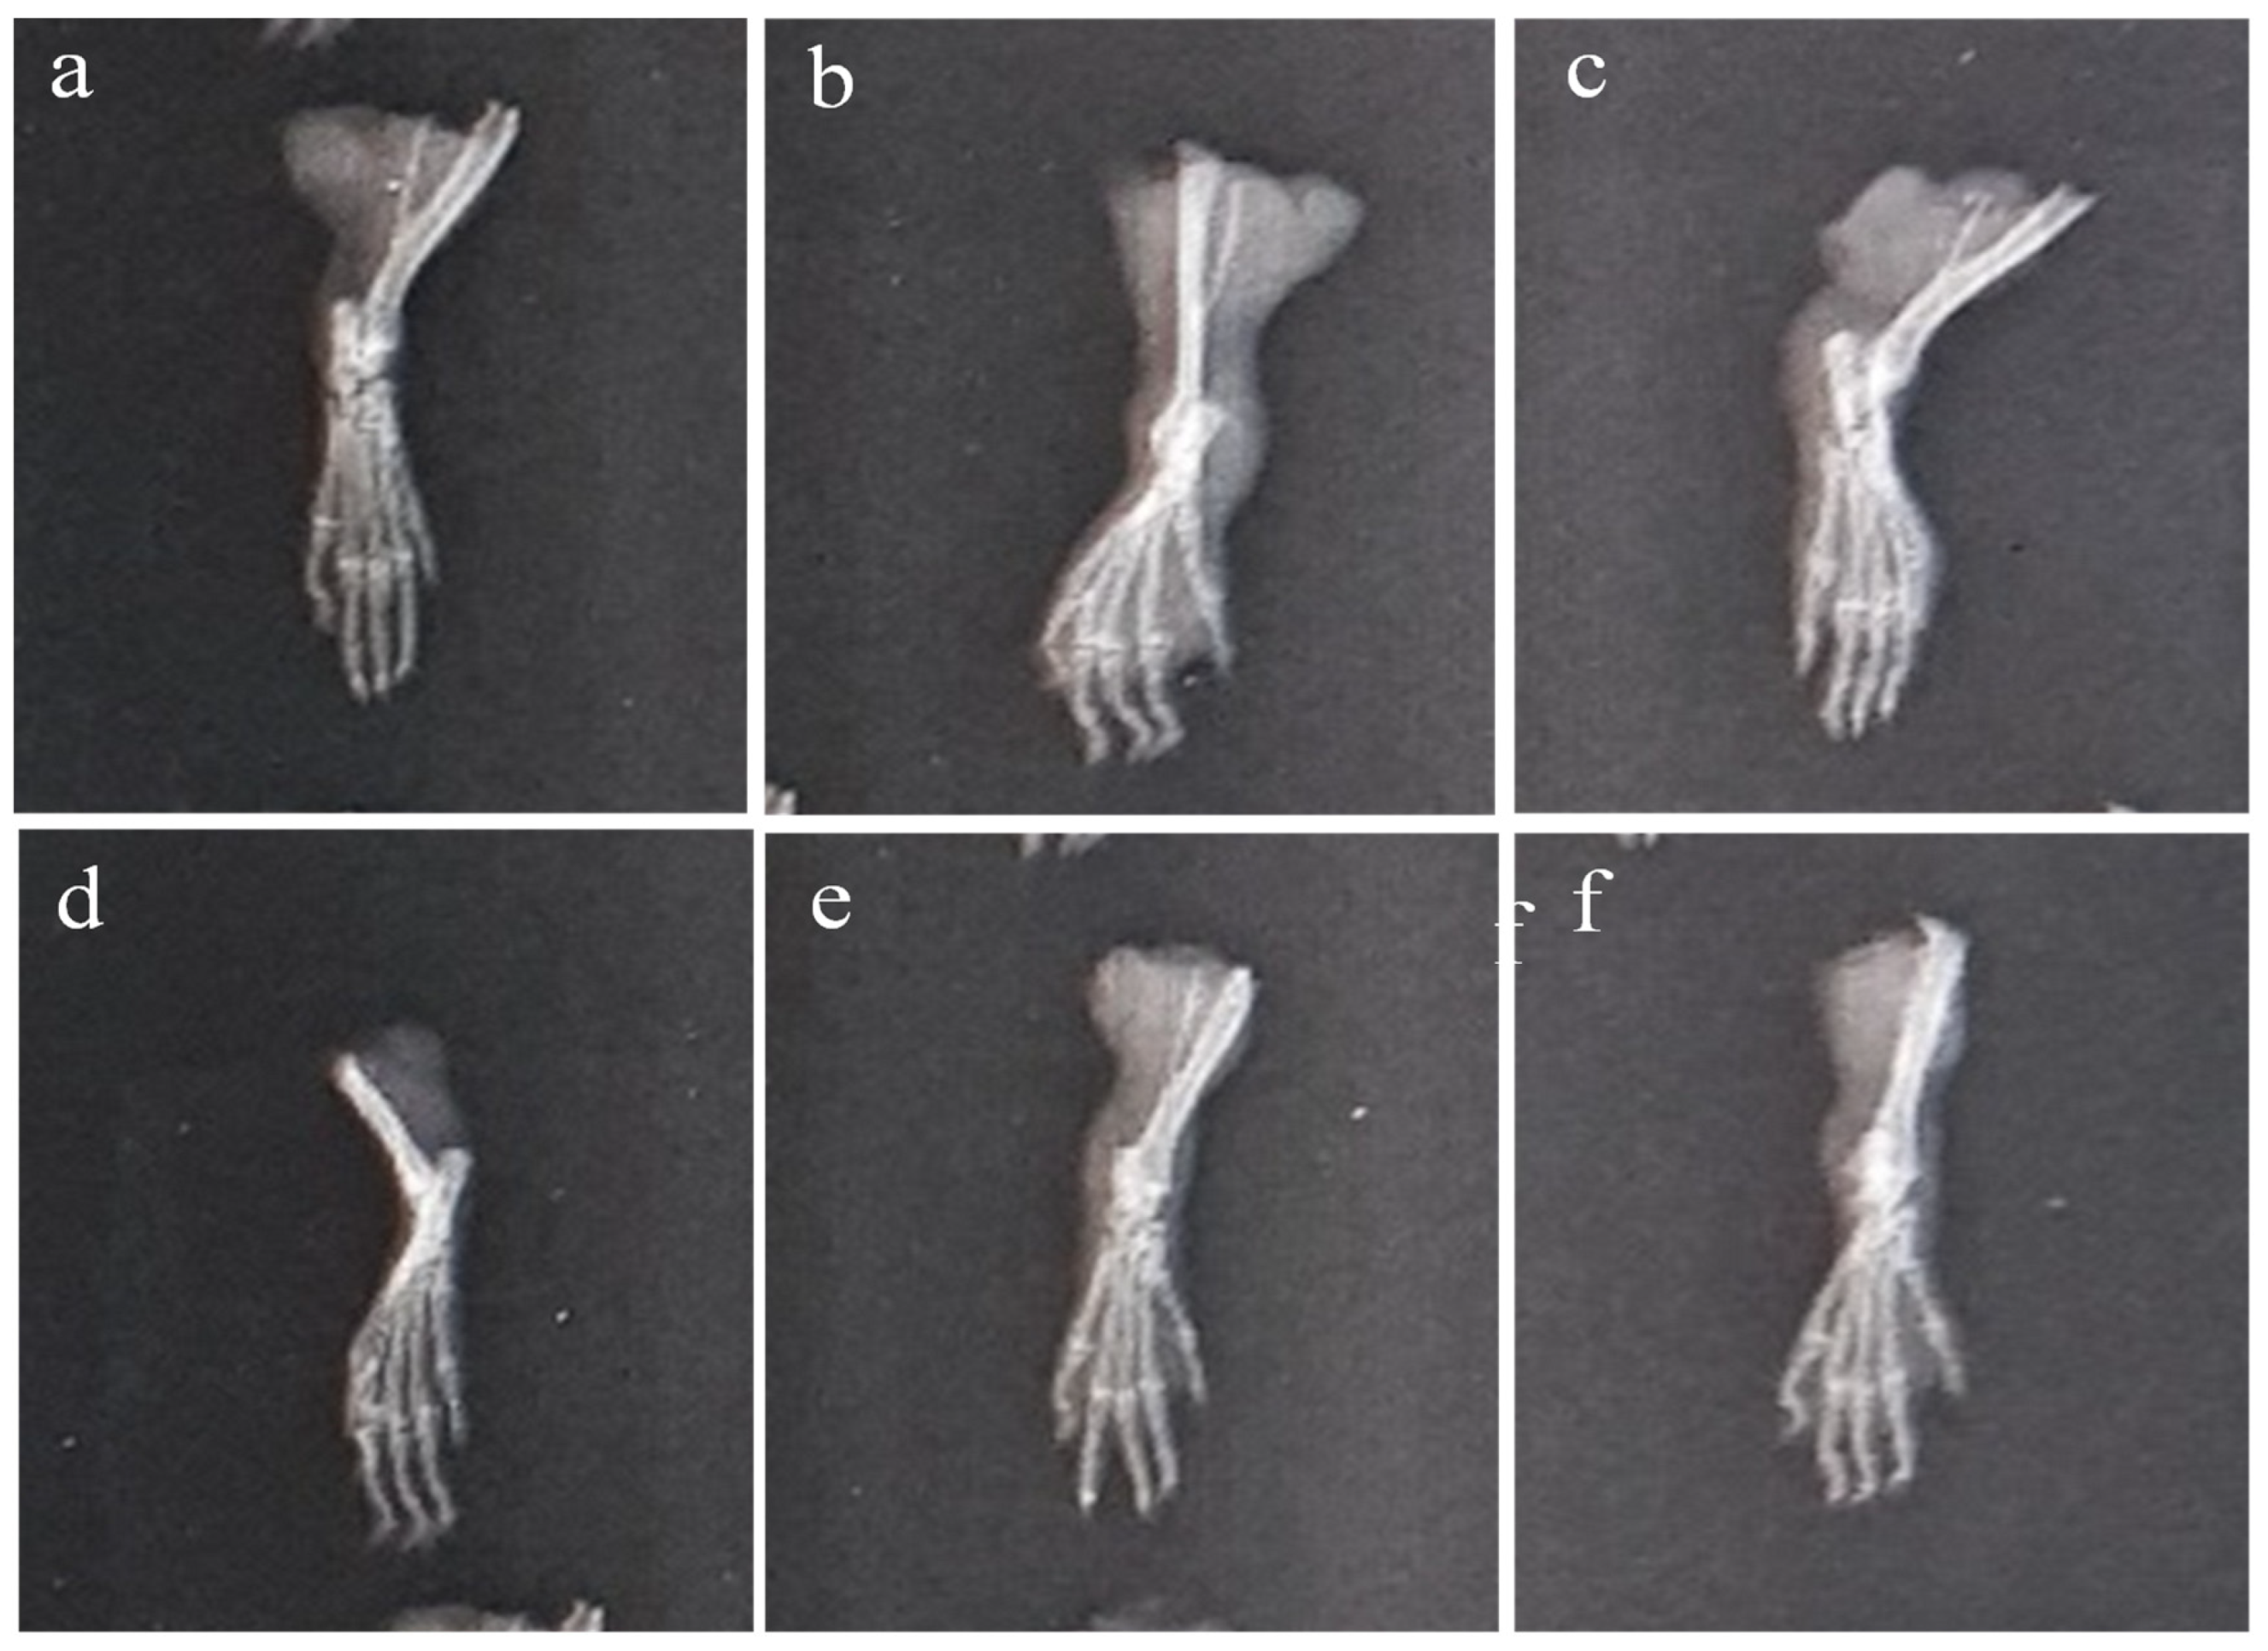

2.6.3. X-ray of Left Hind Paw

The paws’ X-ray radiographs on the 28th day are shown in Figure 11. This revealed extensive erosion, soft tissue swelling, and joint space narrowing (inter-tarsal joints) in Group-II. The use of plant extract and indomethacin, however, decreased the narrowing of joint space and enhanced the radiographic pattern of the joints. It was discovered that Group-VI animals had better radiographic patterns in the joints than the Group-IV animals.

Figure 11.

X-ray of CFA-induced rat paws: (a) Group-I (normal), (b) Group-II (arthritic control), (c) Group-III (standard), (d) Group-IV (AeOB, 250 mg/kg), (e) Group-V (AeOB, 500 mg/kg), and (f) Group-VI (AeOB 750 mg/kg) on day 28.